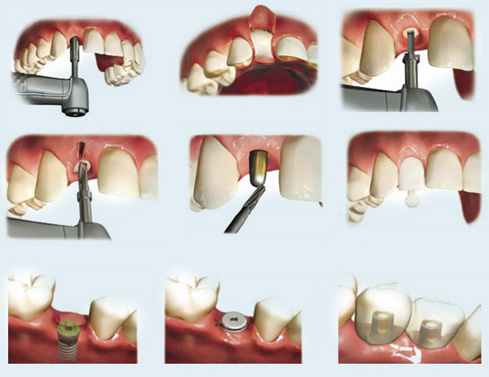

DENTAL TEETH IMPLANT PROCEDURE

June 10, 2019DENTAL TEETH IMPLANT PROCEDURE

Teeth implant therapy is considered to be an invention of the development of the dental industry up to the present. Implant transplantation is fast, safe and effective for those who lose their teeth.

Implant gives you comfort in eating, aesthetic as real teeth and especially limiting the process of bone loss. Should more and more patients use and choose this method. And one of the key determinants of success is teeth implant.

Step 1: Examination, consultation, CT scan of the jaw bone.

The first is that doctors check the general condition of the teeth if there are problems such as periodontal disease, dental treatment should be before transplant. Your doctor will ask about your overall health including cardiovascular, blood pressure, diabetes or radiation therapy. Certainly the patient has many questions to ask before transplant, the doctor will answer you.

Your doctor will ask you to take a 3D CT scan to check your jaw bone density, bone height is appropriate for implant placement. This is important in the diagnosis and planning of effective teeth implant. The doctor will then describe in the film how you can understand where the implants should be placed, how your treatment plan will proceed.

How much the cost of implants, how much to pay, as well as how many implants are covered are all covered in this first appointment.

Step 2: Implant placement schedule.

If you agree with the treatment plan that your doctor offers, you may contact your dentist directly or through a doctor to schedule an appointment. For your work and activities, the dentist will create favorable conditions for you to choose the appropriate time.

Step 3: Teeth implant.

On the date of implantation you have to keep your mood relaxed, eat well and ensure good health. While the dentist has prepared the necessary equipment for the implant from the room, the items are sterile to avoid losing your time as well as to make you feel more comfortable and comfortable. Implant placement takes only 20 minutes with time to extract a tooth.

After transplant, you will be given a prescription to help heal the wound quickly. Just like tooth extraction, you can live and work normally or just rest for a day. If you need more than one surgical procedure, such as extraction, teeth implant, bone grafting, or open sinus surgery, you may need more rest for 3 to 5 days.

Step 4: Temporary restoration during healing.

Are teeth missing during teeth implant? You feel concerned that you have to leave the drum for the duration of the healing period and that the implant integrates the jaw so your dentist will always prepare your teeth temporarily after implanting you. Temporary teeth will help you eat chewing and meet the aesthetic requirements, temporary teeth will help you communicate and live in the process of waiting for the implant cylinder integrated with the jaw bone.

Step 5: Re-examine your doctor.

Approximately 1 week – 10 days after implantation of soft tissue implants (gum) around your implant head will heal. This is a good time to go back to check up, trim and test x-ray.

Step 6: Restore porcelain teeth on the implant pier.

This time is after 3-6 months implant piercing implant. The work is similar to the crown of dental porcelain or conventional bridge. The doctor will advise you the type of dental porcelain suitable as cercon, titan … You can come to dental clinic in 2-4 times, depending on the amount of dental porcelain that time will be different.

Once you have cemented on the impalnt pillar, you have completed the implant. You can have a tooth that has the function, shape and color of your teeth.